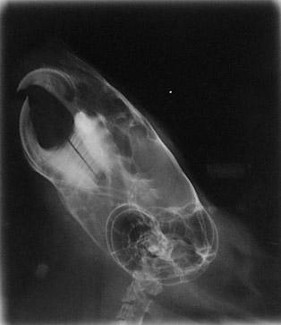

Below are x-rays of both a normal chinchilla and a chinchilla with malocclusion.

Normal

As can be seen, there is a major difference between the chinchilla with normal teeth and the one with malocclusion. The normal x-ray shows teeth meeting in a straight line with little or no curving of either the teeth or the roots. There is no evidence of the roots growing outside of the jaw line.